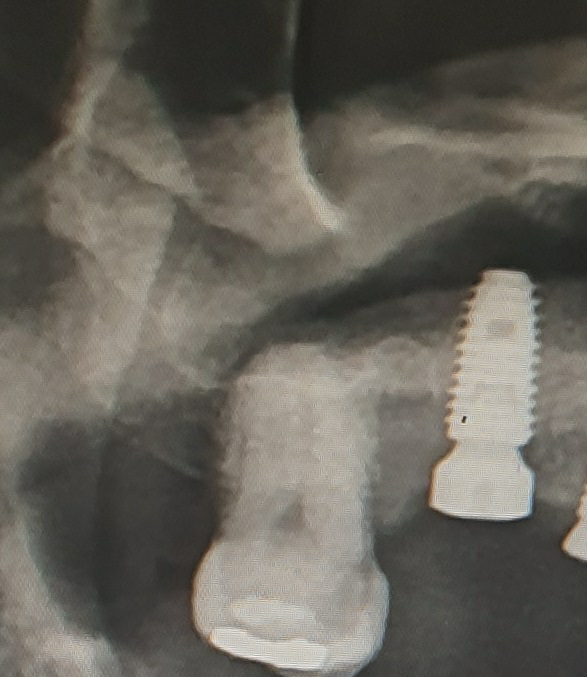

맨 안쪽 어금니는 없어도 되나요

파란색 인플란트 중

노란색 크라운

빨간색 충치

검은색 치아없음

현재 인플란트 중인데요 상악 7번이 충치로 크라운 치료 필요한데 담당 치과의사 분이 사용 안하는 이로 돈들여서 치료필요없고 아프면 발치하면 된다는데요.

• 1번 째 사진

• 2번 째 사진